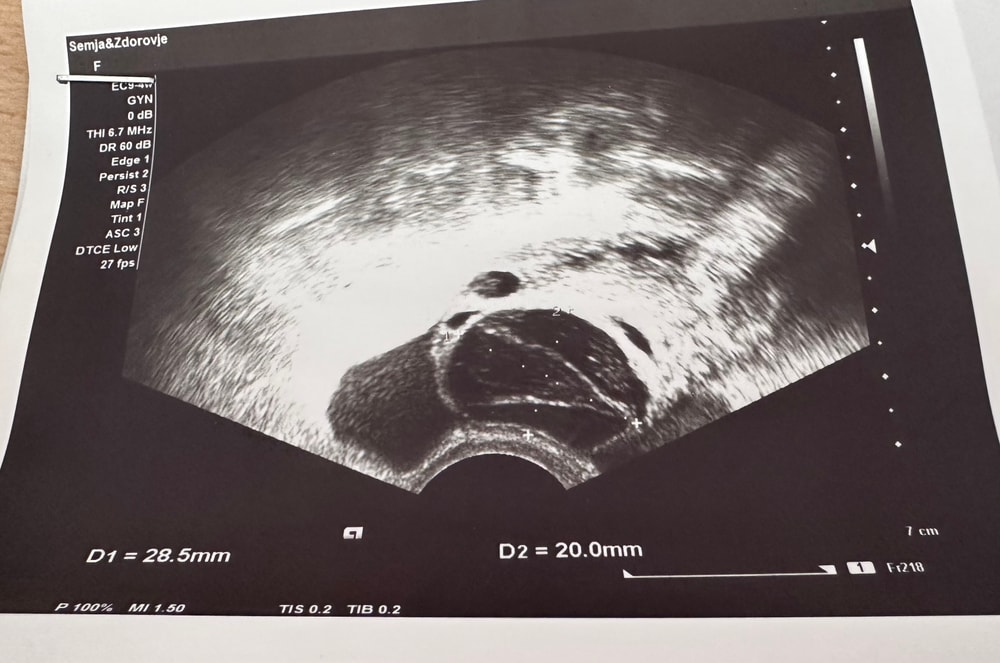

Может кто-то разбирается в узи? Не знаю какая это киста.